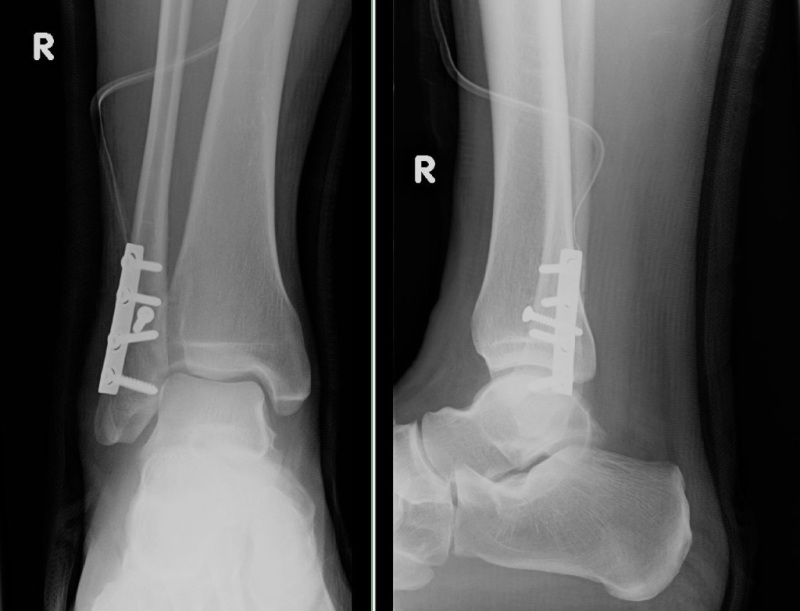

Meine erste Ausfahrt mit meiner XT endete dieses Mal so ...

1. Ausfahrt.JPG

nu hab ich erst mal Pause :cry:

Ich habs nur noch knacksen gehört, da hats mir den Fuß nach ausen gebogen.

die Schrauben sind ja schief drin.

Gute Besserung dem Wadenbeinchen!